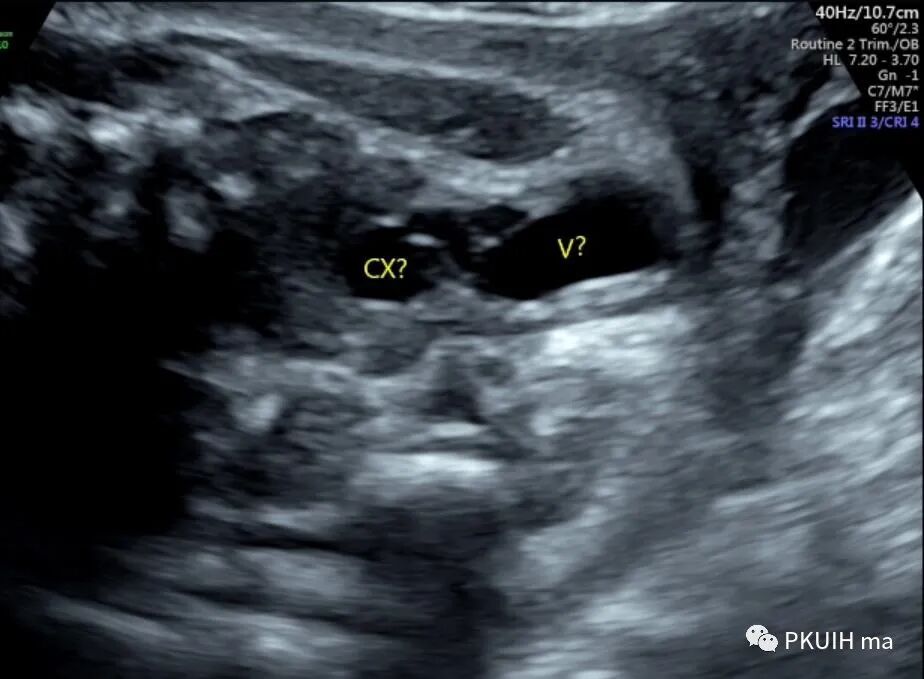

超声显示外生殖器为女性特征,肛门前方见囊性回声,冠状切面显示囊性回声延至会阴处

囊性回声似呈葫芦状,下方大,上方小